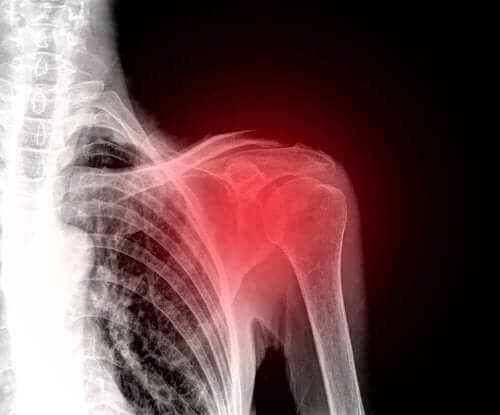

Kiertäjäkalvosimen repeämä on yleinen olkapäävamma keski-ikäisillä. Se onkin näin ollen yksi johtavista olkapääkivun syistä. Tässä artikkelissa kerromme kaiken, mitä kiertäjäkalvosimen repeämästä tulee tietää.

Oireet riippuvat vamman vakavuudesta. Pääasiallinen oire on kuitenkin olkapään kipu ja tämän nivelen kaikkien liikkeiden rajoittuminen.

Joillakin ihmisillä esiintyy ongelmia pääosin yöaikaan; heidän on lähes mahdotonta nukkua sen kyljen puolella, jolla vamma sijaitsee. Myös siistiytymistoimenpiteet kuten hiusten harjaaminen, pukeutuminen ja vaikka peseytyminen ovat huomattavasti vaikeampia.

Kiertäjäkalvosimen repeämä voi johtaa vakaviin komplikaatioihin mikäli sitä ei hoideta ajoissa, sillä liian passiivisena pysyvä raaja surkastuu vielä enemmän. Tämä vaikeuttaa hoitoa jossain määrin. Jos tämä nivel ei pysy riittävästi liikkeessä, se voi johtaa olkapään krooniseen heikkouteen.